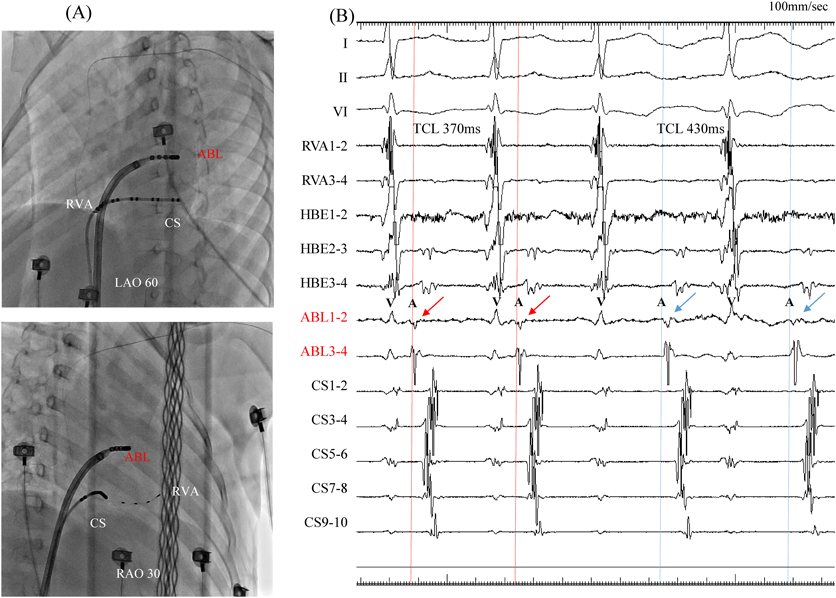

Fig. 4 Fluoroscopic images and intracardiac electrocardiogram of the initial atrioventricular reciprocating tachycardia (AVRT). (A). Upper panel: the left anterior oblique (LAO) view. Lower panel: the right anterior oblique (RAO) view. The ablation catheter is positioned at the site of successful ablation. (B). The intracardiac electrocardiogram revealed that the site of the earliest retrograde atrial activation was at ABL1 and ABL2. Conduction through the left lateral accessory pathway was interrupted at 4.3 sec with a radiofrequency application, but AVRT persisted. The pattern of the atrial activation and tachycardia cycle lengths had changed, although the earliest atrial activation remained adjacent to the ablation catheter in the left atrium.

ABL, ablation catheter; CS, coronary sinus electrode; LA, left atrium; LV, left ventricle; RVA, right ventricular apex electrode; TCL, tachycardia cycle length.